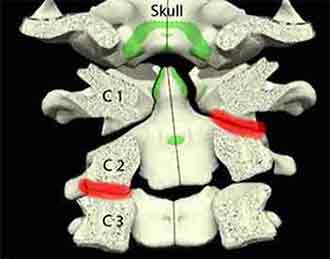

A few weeks ago a young lady came to see me with an acute neck strain. She could hardly move her neck in any direction. She was an actress playing a part in a musical where her character was an evil old lady with a crooked posture. This had induced her problem. After one treatment she was relieved of the pain and following the second session two days later she was completely out of pain and her normal range of mobility was restored.

Long term neck stiffness is often due to a mal-positioning of the vertebrae accompanied by some degree of joint rigidity. The neck muscles are especially prone to hypertonus and as such need to be softened, stretched and mobilized.